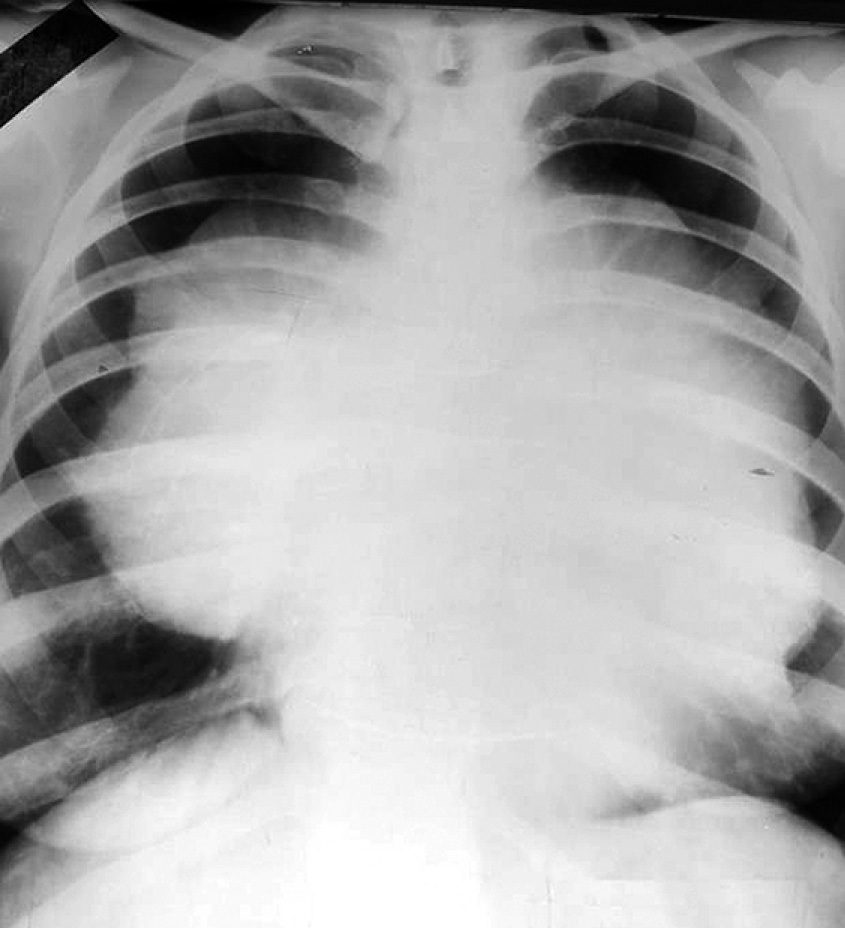

Из анамнеза известно, что больная в течение двух последних месяцев стала отмечать появление одышки при физической нагрузке. Состояние ухудшалось, дополнительно появились отёки на лице к вечеру. При обращении к участковому терапевту в поликлинику по месту жительства выполнена рентгенография грудной клетки, в результате выявлено массивное опухолевое образование в средостении (рис. 1, 2).

Рис. 1. Рентгенография грудной клетки в прямой проекции.

Fig. 1. X-ray of the chest in direct projection.